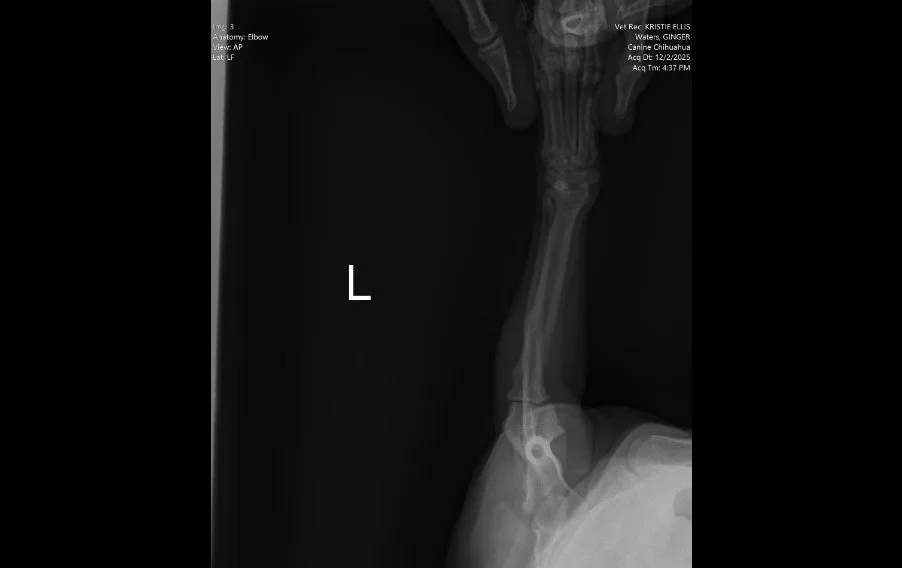

Lateral radiograph of the left elbow and antebrachium in a dog with no evidence of fracture or bone lysis

Image 3. Lateral radiograph of the left elbow and antebrachium.

Radiographs (Images 1–4) of the left forelimb, including the carpus, elbow, and shoulder identified:

• Mild degenerative joint disease (arthritis)

• Decreased shoulder joint space

• No fractures, masses, or bone lysis

Based on these findings, Ginger was treated for osteoarthritis. However, her clinical progression did not match the imaging results.